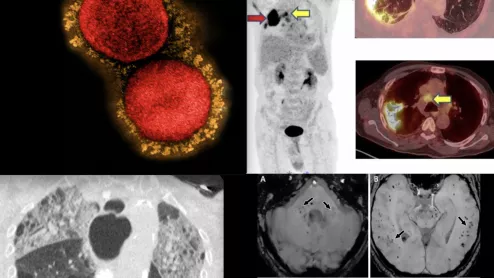

The REVEAL study has been assessing the sensitivity and specificity of iodine 124 evuzamitide (I 124 evuzamitide), a PET agent capable of visualizing signs of cardiac amyloidosis on imaging.